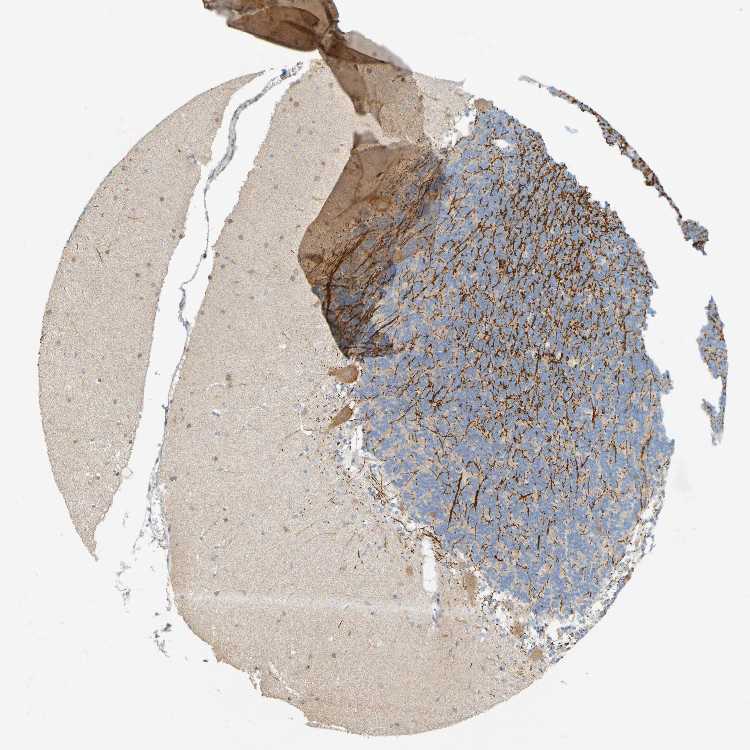

CEREBELLUM - Antibody stainingi

Antibody staining in the annotated cell types in the current human tissue is reported as not detected, low, medium, or high, based on conventional immunohistochemistry profiling in selected tissues. This score is based on the combination of the staining intensity and fraction of stained cells.

Each image is clickable and will lead to virtual microscopy that enables deeper exploration of all samples and also displays staining intensity scores, fraction scores and subcellular localization as well as patient and tissue information for each sample.

Antibody HPA012499Antibody CAB009345

Processes in granular layer -High

Processes in molecular layer -Not detected

Processes in white matter -High

Synaptic glomeruli - capsule -High

Synaptic glomeruli - core -Not detected